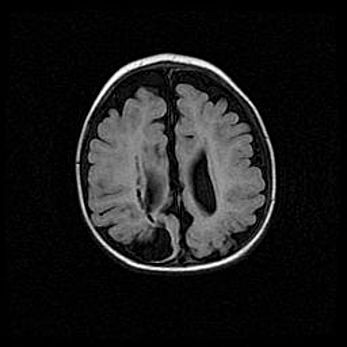

Сообщающаяся гидроцефалия. Кистозная энцефаломаляция головного мозга.

Возраст: 3 месяца 4 дня

Вес: 3100 г

Пол: женский

Окружность головы: 34 см

Срок гестации: 31 неделя

Кистозная энцефаломаляция головного мозга - одна из форм поражения головного мозга в детском возрасте. Характеризуется возникновением множественных и распространённых кист в коре, белом веществе и подкорковых образованиях головного мозга у плодов, новорождённых и детей раннего возраста. Развитие кистозной энцефаломаляции связано с внутриутробной асфиксией и гипотонией, родовой травмой, тромбозом синусов, пороками развития сосудов, инфекциями, сепсисом и другими причинами. Наиболее значимые инфекционные агенты: вирусы простого герпеса, цитомегалии, краснухи, токсоплазмы, энтеробактерии, золотистый стафилококк и другие.